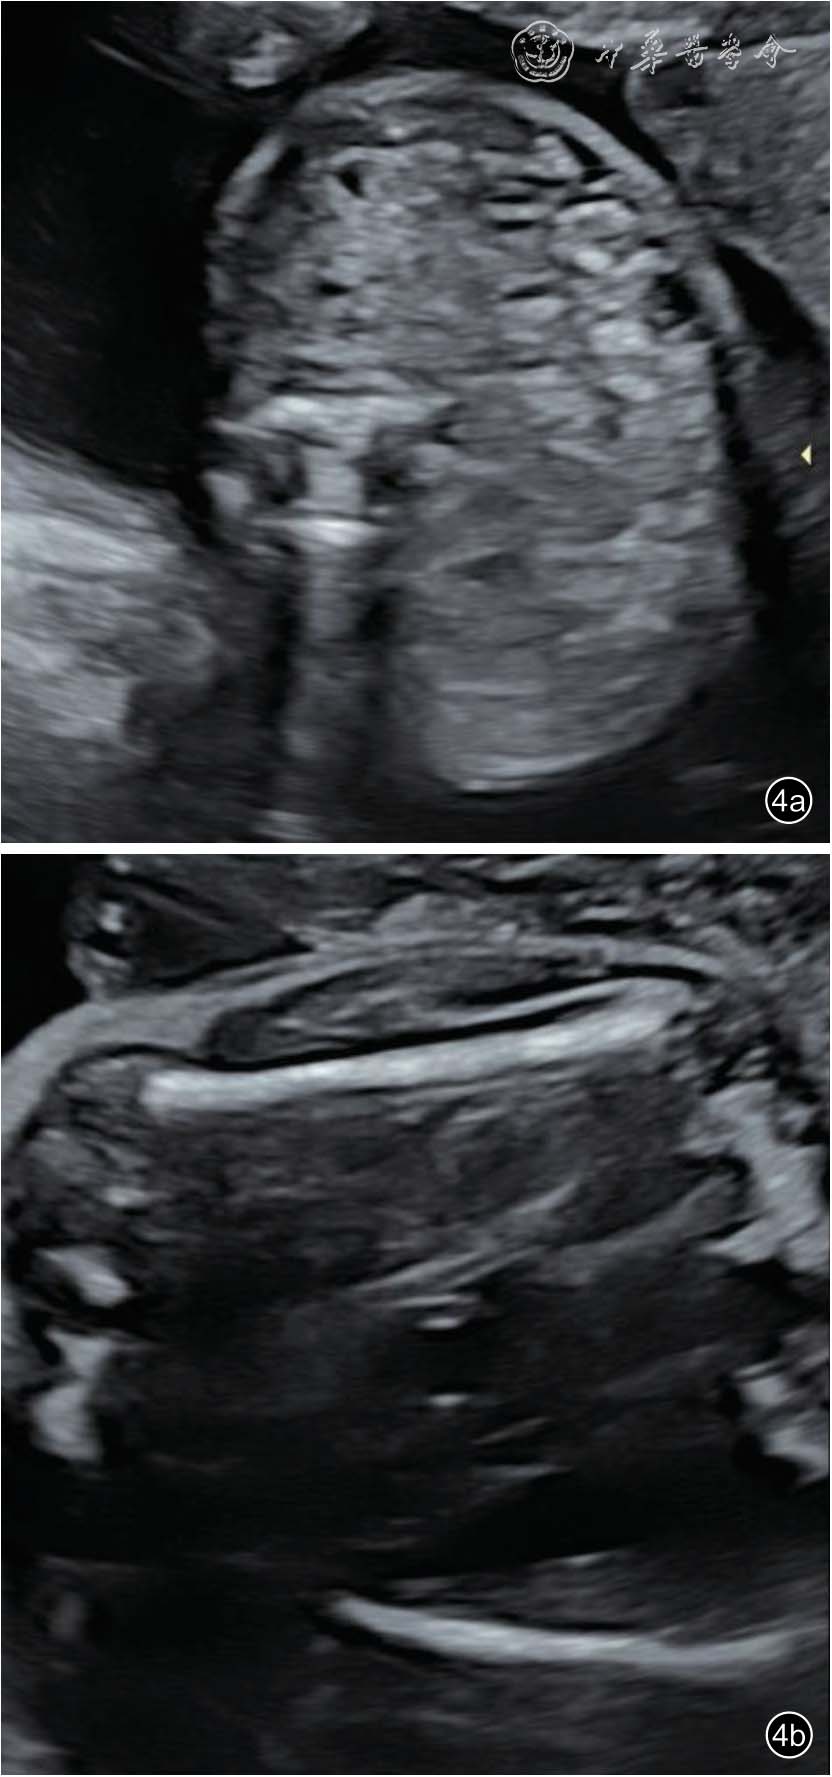

图4 双胎贫血-红细胞增多序列征胎儿孕22+5 周产前超声图像可见供血儿部分肠管肠壁回声增强(图a),略低于骨骼回声(Ⅰ级)(图b)